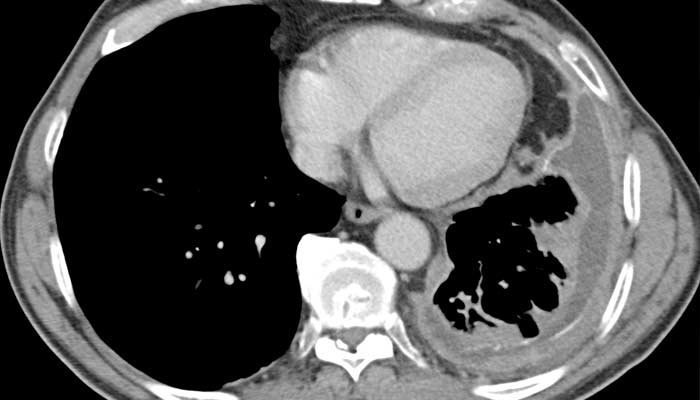

Anesthesia was administered in childbirth for the first time in 1847 at the Boston Lying-In Hospital. In 1929, the Peter Bent Brigham Hospital introduced the world to the Drinker respirator (or iron lung), which successfully saved a young polio patient’s life. In the early 1990s, a team of surgeons participated in the first wave of successful lung, heart-lung and triple organ transplants at BWH. Thoracic surgeons here were also among the first to develop minimally invasive lung surgery and, more recently, image-guided thoracic surgery (iVATS).

These milestones had their infancy in the research laboratories of BWH where physician-scientists continue to discover and test respiratory treatments and cures, including landmark studies in chronic obstructive pulmonary disease (COPD) and asthma. It was only fitting that clinical and research expertise for lung disease merged at BWH in 2015. The Lung Center and its affiliated Lung Research Center launched, heralding a strong connection between respiratory specialists and sub-specialists throughout BWH in clinical care and innovation and marking a new era in lung health for adults with respiratory disease.